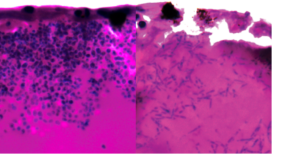

Speaking on the Future Leaders award, Dr De Franco said: “When beta-cells die, it stops the body producing insulin which regulates our blood sugar, affecting diabetic patients. I’ll be studying the DNA of people with extreme forms of beta-cells deaths which results in diabetes developing soon after birth, to help us identify genes essential for these cells’ survival.